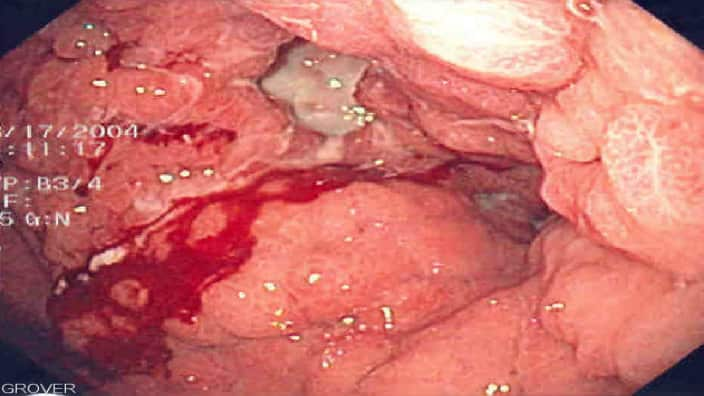

2- Các dấu hiệu của ung thư dạ dầy

Trong giai đoạn đầu, đâu là dấu hiệu ung thư dạ dầy?

Đa số bệnh nhân chỉ biết mình bị ung thư dạ dầy trong gia đoạn cuối vì giai đoạn đầu các dấu hiệu không rõ ràng thành ra ít người chú ý.

- Nặng hơn nữa là ói ra máu, đi ngoài phân đen.

Giai đoạn 1: Tế bào ung thư chỉ mới cư trú ở bề mặt dạ dầy, rất khó phát hiện.